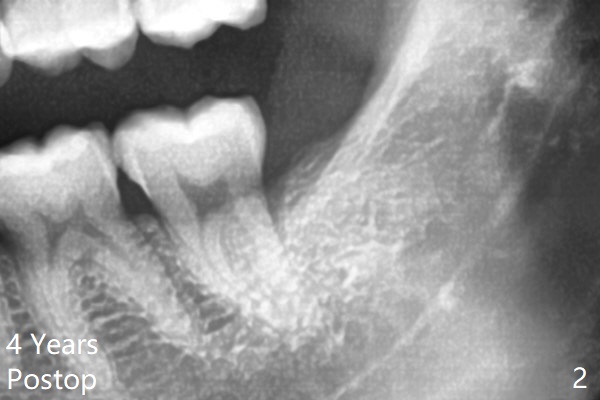

Osteogen plug is placed in the sockets of #17 and 32 post extraction.  The sockets heal 4 years later (Fig.2).